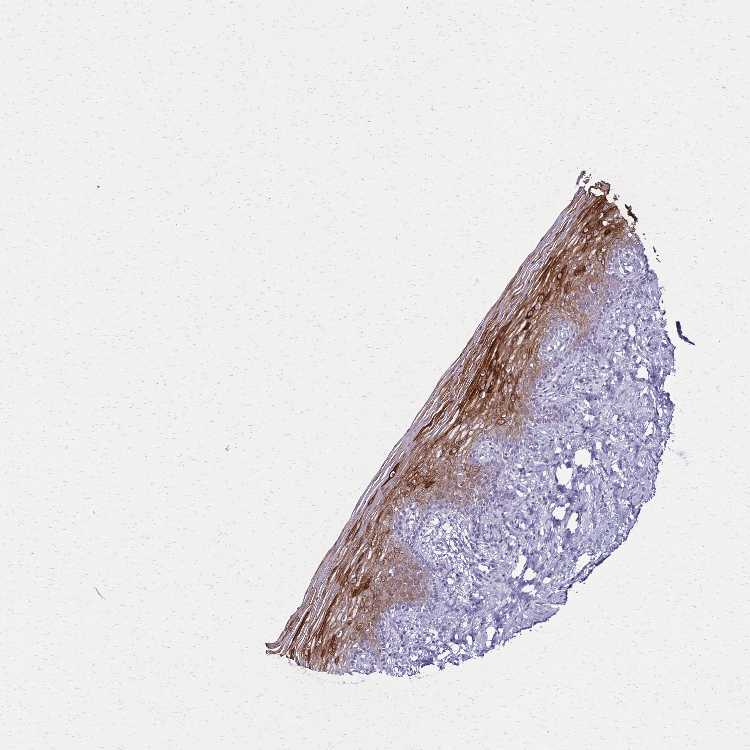

VAGINA - Antibody stainingi

Antibody staining in the annotated cell types in the current human tissue is reported as not detected, low, medium, or high, based on conventional immunohistochemistry profiling in selected tissues. This score is based on the combination of the staining intensity and fraction of stained cells.

Each image is clickable and will lead to virtual microscopy that enables deeper exploration of all samples and also displays staining intensity scores, fraction scores and subcellular localization as well as patient and tissue information for each sample.

Antibody CAB037321

Squamous epithelial cells High